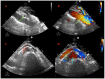

Nutcracker and Wilkie syndromes are rare mesoaortic compression entities, and their association is even less common. Data on interventional treatment of these pathologies are still scarce, but results from limited case series are encouraging. We report the case of a previously healthy 45-year-old woman diagnosed with nutcracker and Wilkie syndromes who presented with macroscopic hematuria, intermittent pain in the left flank and hypogastric region, postprandial nausea, and unexplained significant weight loss. A successful endovascular approach with stent implantation in the left renal vein was performed, but the stent migrated toward the left kidney, and this acute complication was managed through an interventional strategy as well. At the three-month follow-up, the patient described a marked improvement in all symptoms, except for the macroscopic hematuria. As it was our strong belief that the approach was efficient, we further investigated the "hematuria", which eventually led to the diagnosis of endometrial carcinoma. A hysterectomy and bilateral adnexectomy were planned, and chemoradiotherapy was initiated with the goal of preoperative tumor reduction. To our knowledge, this is the first reported case in which both Wilkie and nutcracker syndromes were effectively treated by stent implantation in the left renal vein, complicated with very early stent migration due to inadequate apposition to the less compliant venous lumen. The treatment of the duodenal compression was indirectly included in the stenting of the left renal vein, as reclaiming the venous lumen widened the aortomesenteric angle. The aim of this review is to discuss our center's transcatheter experience with these rare disorders and explore the literature in order to establish the benefits and limitations of such an approach.